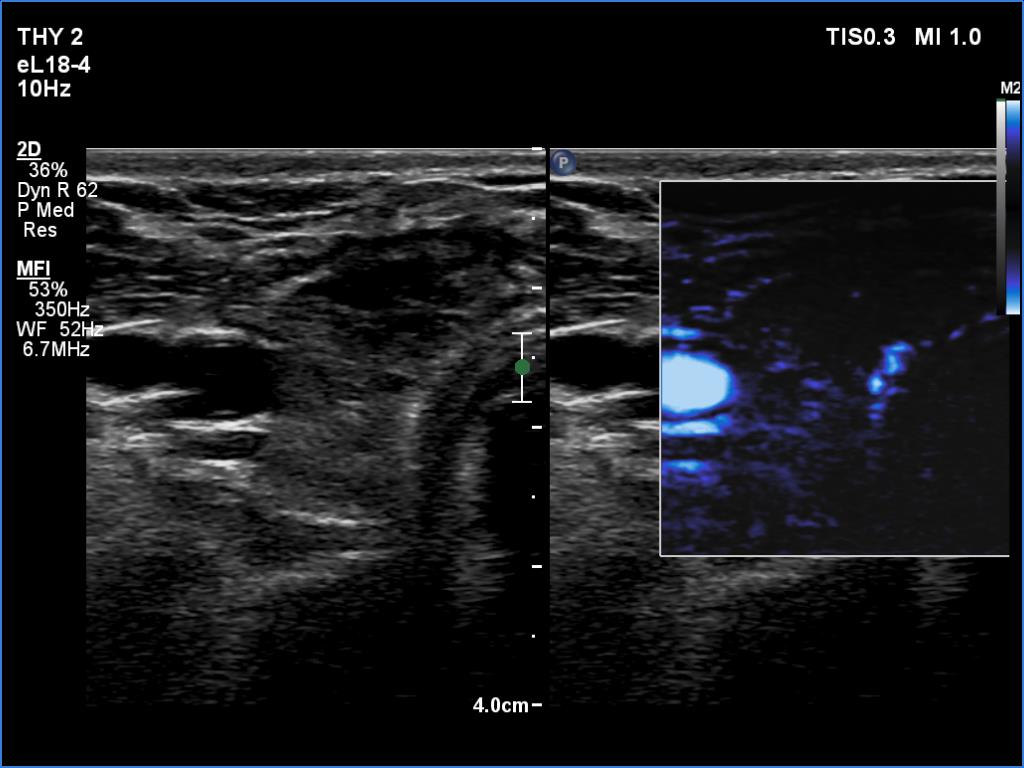

Second examination four weeks after surgery (second row of images):

Clinical data: The patient had no complaints.

Palpation: no abnormality.

Laboratory tests: TSH 3.99 mIU/L.

Ultrasonography. Regenerative tissue replaced the right lobe. The left lobe remained unchanged.

Suggestion: THS in 6 months.